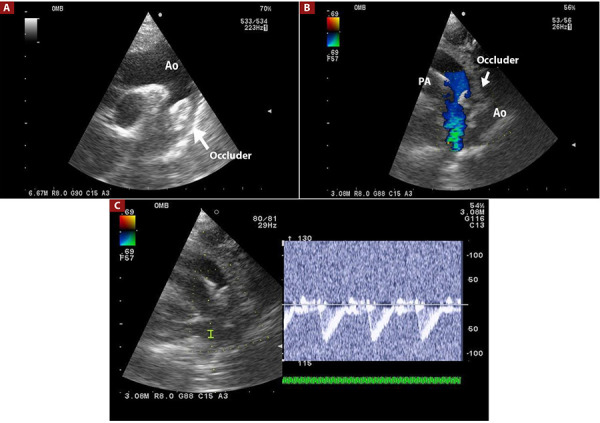

Objetive: Percutaneous occlusion of patent ductus arteriosus (PDA) has classically been performed entirely by fluoroscopy, however in recent years, transthoracic echocardiography (TE) has been used as an aid to fluoroscopy or entirely by echocardiography, which avoids access of femoral artery, use of contrast and decrease in time and dose of radiation exposure. The objective of this study was to evaluate the success rate with the use of TE in percutaneous PDA closure.

Material and method: Descriptive, comparative, retrospective study between patients in whom PDA closure was performed with fluoroscopy plus angiography (group 1) and fluoroscopy plus ET (group 2), between January 2018 and December 2022. The data were obtained from the clinical history electronic and procedure report.

Results: One hundred eight patients were analyzed, fluoroscopy group (n: 57) and TE (n: 51). The success rate in PDA occlusion using TE was 100% and 98% for the fluoroscopy group, with no statistically significant difference The average age of group 2 was 2.9 years, while the average age of group 1 was 5 years (p=0.001), the average fluoroscopy time in group 1 was 16.9 min and 4.71 min in group 2 (p < 0.001); the fluoroscopy dose in group 1 was 68.98 mGy and 5.17 mGy in group 2 (p<0.001). Krichenko, but without significant difference in both groups.

Conclusions: The success rate of percutaneous PDA closure using echocardiography and fluoroscopy is appropiate, with a success rate similar to the classic technique. In addition, it makes it possible to reduce the dose and time of fluoroscopy, avoid the use of contrast, and access the femoral artery.